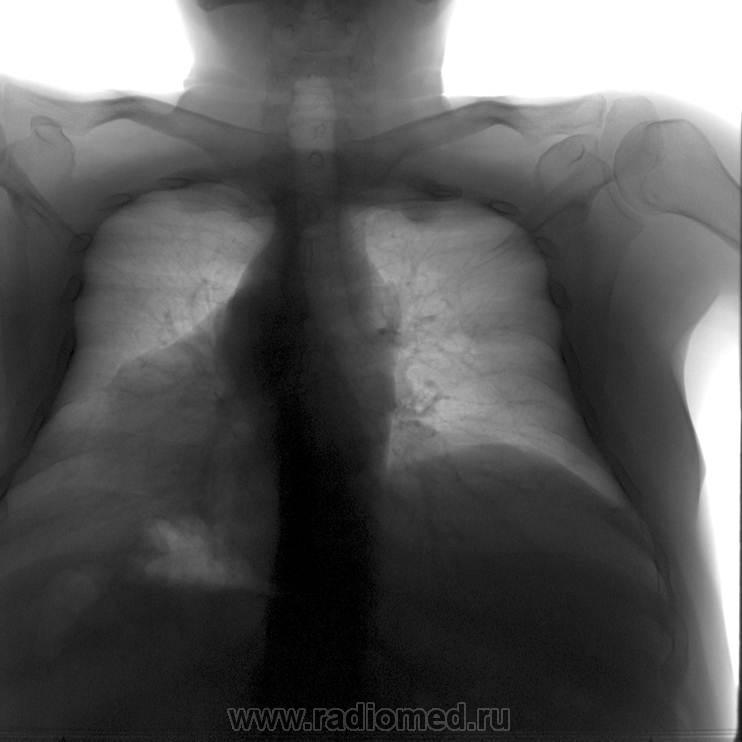

На ребре?

Zorg wrote:

На нем, родимом, да еще и в сторону грудной полости преимущественно...вот и весь периферический рак....